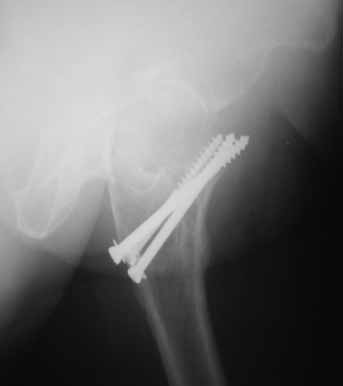

На консультации вот такие снимки. Больная 72 года. упала в быту 26 декабря 2010г.  Оперирована 30 декабря 2010г. в одном из стационаров края. Назначили дополнительное обследование, а пока хотелось-бы услышать мнение по-поводу возможностей сохранения головки. Больная из льготного контингента, т.е. современные констукции и эндопротез маловероятны.